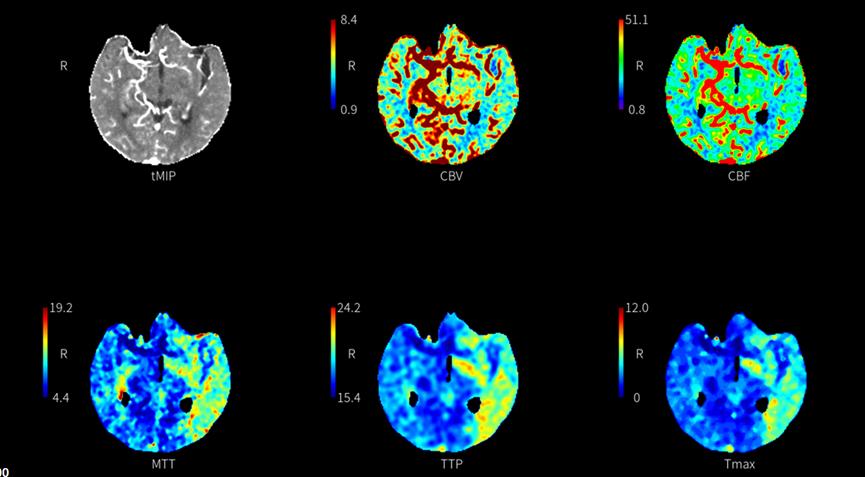

神经内科董万利主任带领团队对胡大爷的病情进行了分析评估。患者头颅磁共振发现左侧大脑中动脉供血区多发脑梗死,CTA+CTP检查提示:左侧颈内动脉颅内段混合斑块,管腔中-重度狭窄,最狭窄处接近闭塞;左侧大脑中动脉供血区缺血性灌注异常。诊断为:“脑梗死,左侧颈内动脉颅内段次全闭塞”。